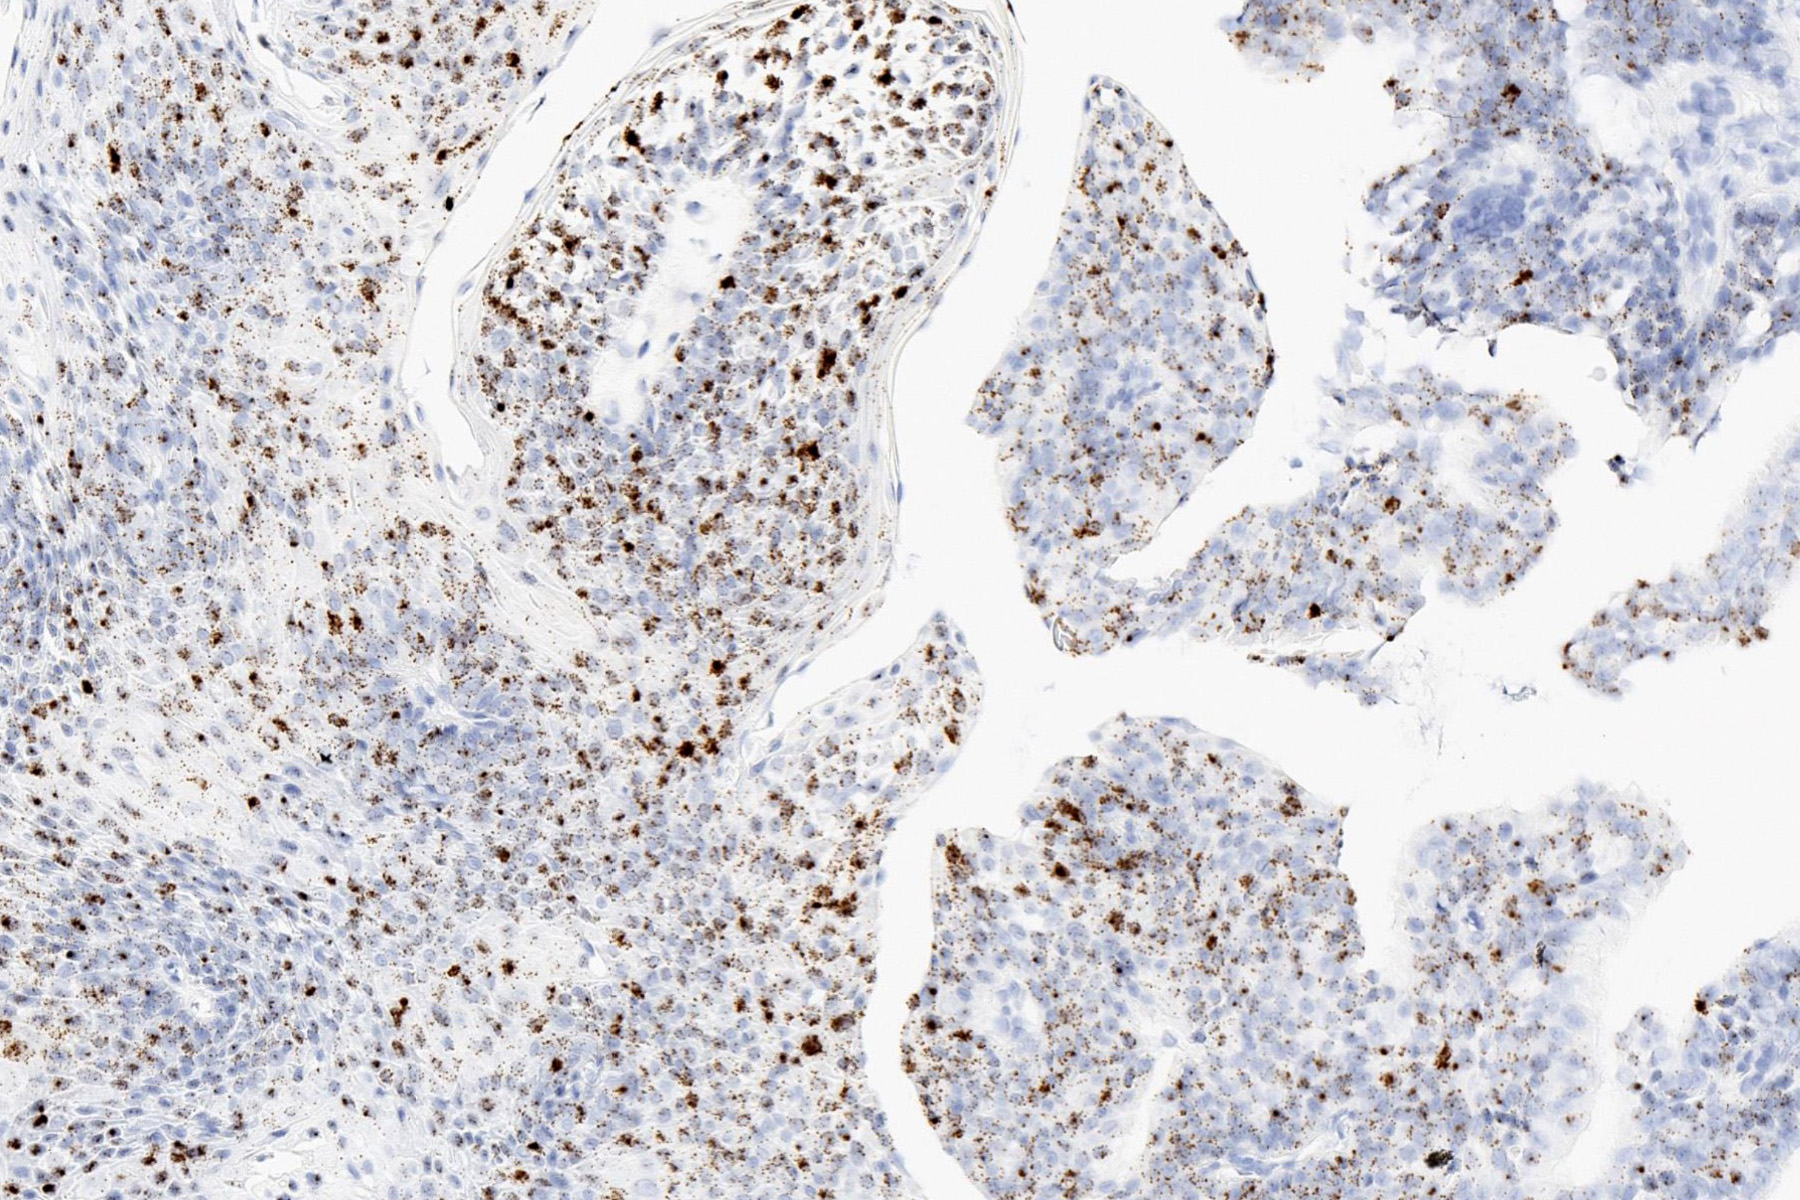

Positive stains

- RNA or DNA in situ hybridization for low risk HPV is typically positive

- Integrated pattern detected by DNA in situ hybridization is associated with increased risk of recurrence in pediatric patients (Head Neck Pathol 2012;6:3)